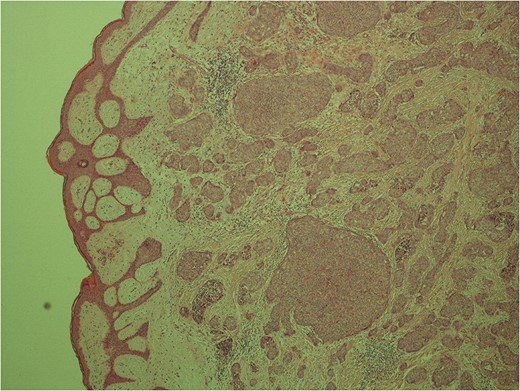

High power image of the dermal nests of tumour showing solid islands of invasive breast carcinoma.